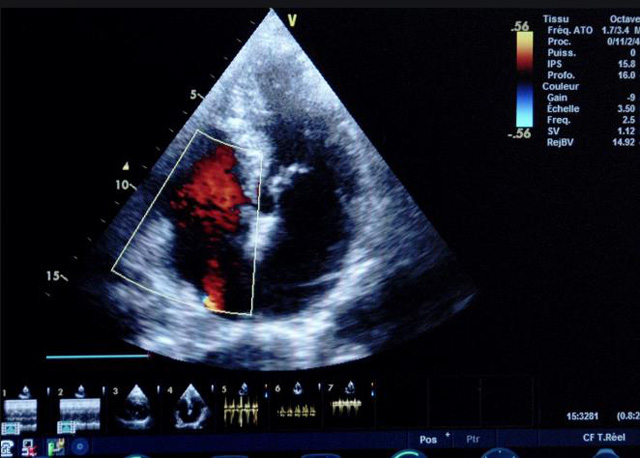

二、彩色室壁運(yùn)動(dòng)分析

(一)基本原理彩色室璧運(yùn)動(dòng)分析,從整體散射數(shù)據(jù)中識(shí)別心內(nèi)膜邊界,并與前一幀彩色不同,心臟收縮或舒張期開始到結(jié)束時(shí)心內(nèi)膜的全部過程。每一次順序顯示結(jié)束后,原來的彩色自動(dòng)消失,以便進(jìn)入下一個(gè)顯示過程。其結(jié)果是獲得對(duì)應(yīng)于每一個(gè)心動(dòng)周期的彩色顯示,描繪特定周期內(nèi)室壁運(yùn)動(dòng)的時(shí)間運(yùn)動(dòng)軌跡。

(二)操作步驟根據(jù)背向散射數(shù)據(jù)中將心內(nèi)膜運(yùn)動(dòng)的位移過程分類為組織或血液的原理,邊緣檢測(cè)跟蹤心內(nèi)膜和血液的界面。橙色表示收縮期的開始,收縮期不同時(shí)相逐幀顯示色彩均疊加在收縮末期最后一幀圖像中。檢查時(shí),可按以下步驟進(jìn)行:

①顯示較為理想的二維圖像,常用切面有心尖四腔心、二腔心、左心室長(zhǎng)軸和左心室乳頭肌水平短軸切面。

②啟動(dòng)AQ系統(tǒng),啟動(dòng)后適當(dāng)?shù)卣{(diào)節(jié)增益補(bǔ)償,顯示心內(nèi)膜。

③啟動(dòng)CK系統(tǒng),啟動(dòng)后劃定感興趣區(qū)域。同時(shí)記錄的心動(dòng)圖R波頂點(diǎn)為舒張末期,T波終點(diǎn)為收縮末期,顯示RT間期的CK彩階圖,連續(xù)記錄3~ 5個(gè)心動(dòng)周期。

④對(duì)所獲圖像和數(shù)據(jù)進(jìn)行分析和計(jì)算。

(三)檢測(cè)節(jié)段性室壁運(yùn)動(dòng)異常,研究冠心病患者左心室功能和分析局部室壁運(yùn)動(dòng)過程中。測(cè)量每一節(jié)段室壁的運(yùn)動(dòng)量,運(yùn)動(dòng)正常的節(jié)段彩帶色彩均勻?qū)哟喂庹_\(yùn)動(dòng)減弱的節(jié)段,厚度薄層次不全。心內(nèi)膜位移幅度和速度均減低。心內(nèi)膜位移幅度和速度甚低或難以測(cè)得。正常的多層彩帶消失,呈現(xiàn)紅色色帶,心內(nèi)膜位移呈負(fù)向,幅度和速度亦減低。急性心肌梗死的患者中可用于識(shí)別存活心肌抑或壞死心肌。多巴酚丁胺負(fù)荷試驗(yàn)存活心肌的心內(nèi)膜位移幅度增高,停藥后即消失,而壞死心肌則無上述表現(xiàn)。實(shí)時(shí)檢查冠心病的節(jié)段性室壁運(yùn)動(dòng)異常,有時(shí)候通過發(fā)現(xiàn)局部心肌運(yùn)動(dòng)的時(shí)相異常,對(duì)于心臟傳導(dǎo)障礙的診斷也可能有幫助。